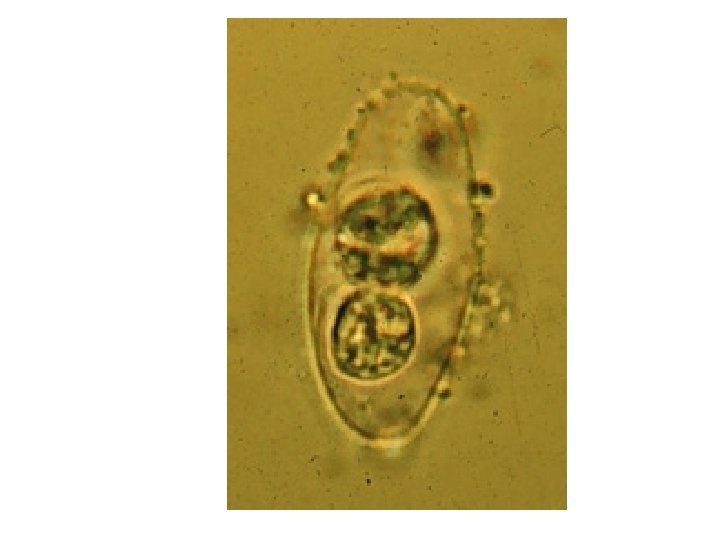

Morphology: =Oocyst elongate ovoidal-shape with moderate constriction in one end giving a charac. “Bottle with short neck” appearance =20 – 33 u L X 10 – 19 u W =Cyst wall double-layered, smooth, thin & colorless =Unsegmented oocyst contains spherical mass of granule with visible nucleus =Mature oocyst has 2 sporocyst and each contains 4 cresent-shaped sporozoites

Isospora belli Microscopy • Wet mount – Usually contains granular zygote – Occasionally more mature sporulated oocyst with – 2 sporocysts – 4 sporozoites each – Oval measuring 20 -23 x 1019µm